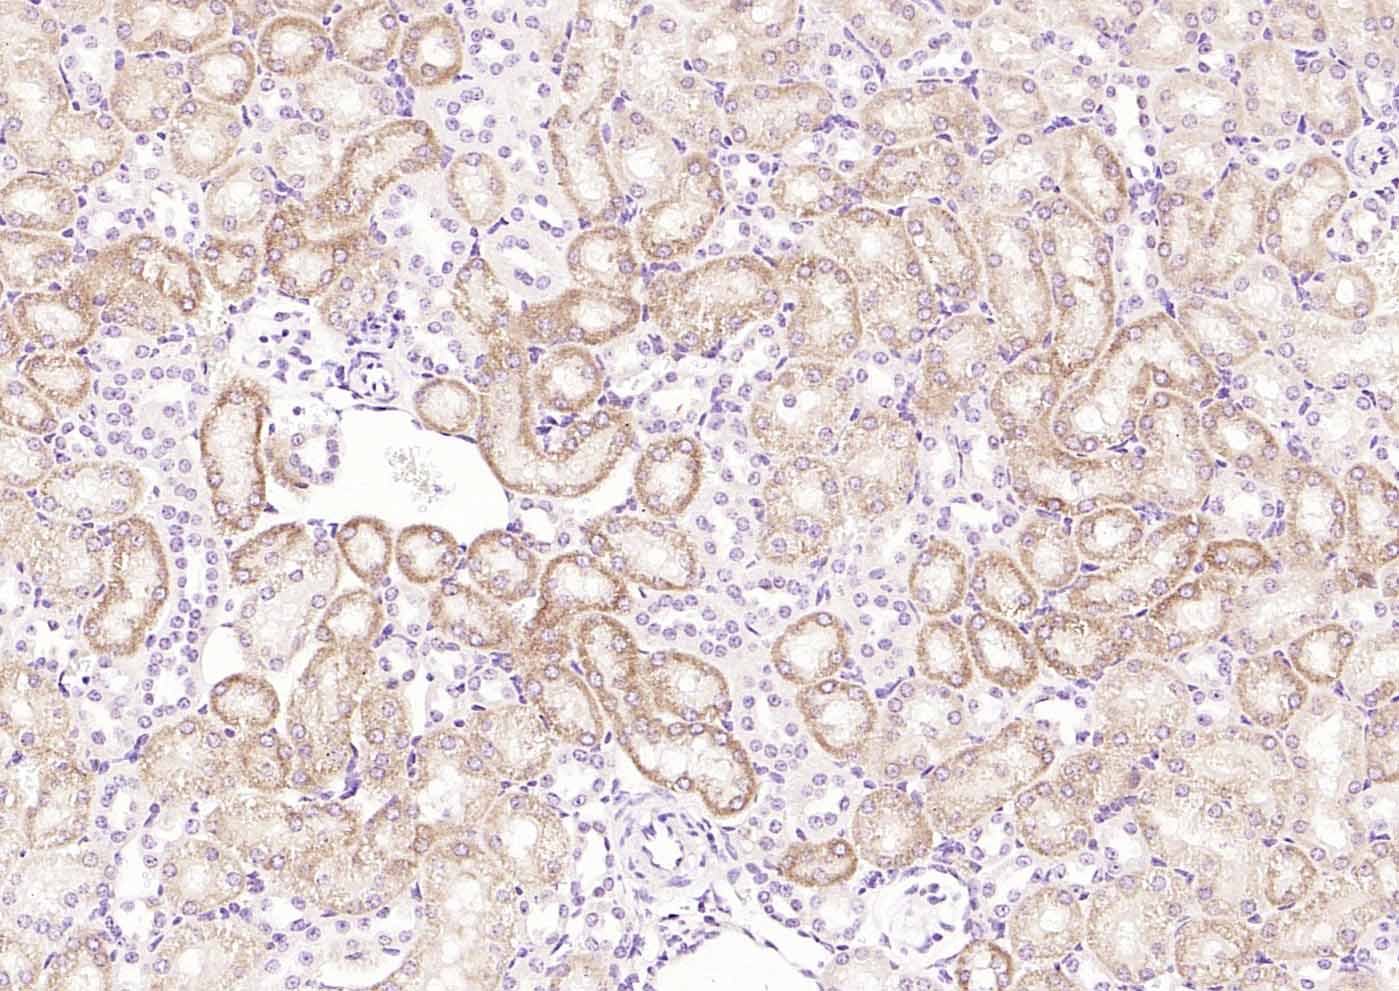

Paraformaldehyde-fixed, paraffin embedded (rat kidney); Antigen retrieval by boiling in sodium citrate buffer (pH6.0) for 15min; Block endogenous peroxidase by 3% hydrogen peroxide for 20 minutes; Blocking buffer (normal goat serum) at 37°C for 30min; Incubation with (RelB) Polyclonal Antibody, Unconjugated (bs-3562R) at 1:200 overnight at 4°C, followed by operating according to SP Kit(Rabbit) (sp-0023) instructionsand DAB staining.